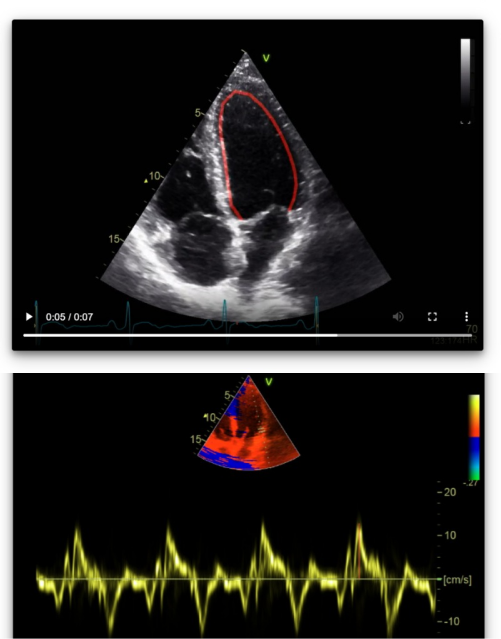

A*STAR is dedicated to leveraging the power of multi-modal AI and data science to promote and sustain healthy living. We have a multitude of research cohorts on Asian-centric populations and diseases drawing from a rich set of data sources.

Through innovative data aggregation and analytic approaches, we aim to empower individuals to make more personalized decisions about their health and disease from prevention to screening, diagnosis, monitoring and intervention.